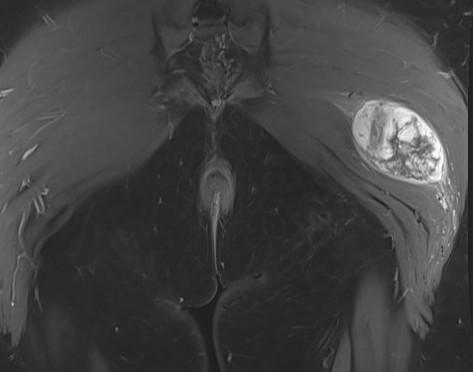

MRI

Sarcoma buttock